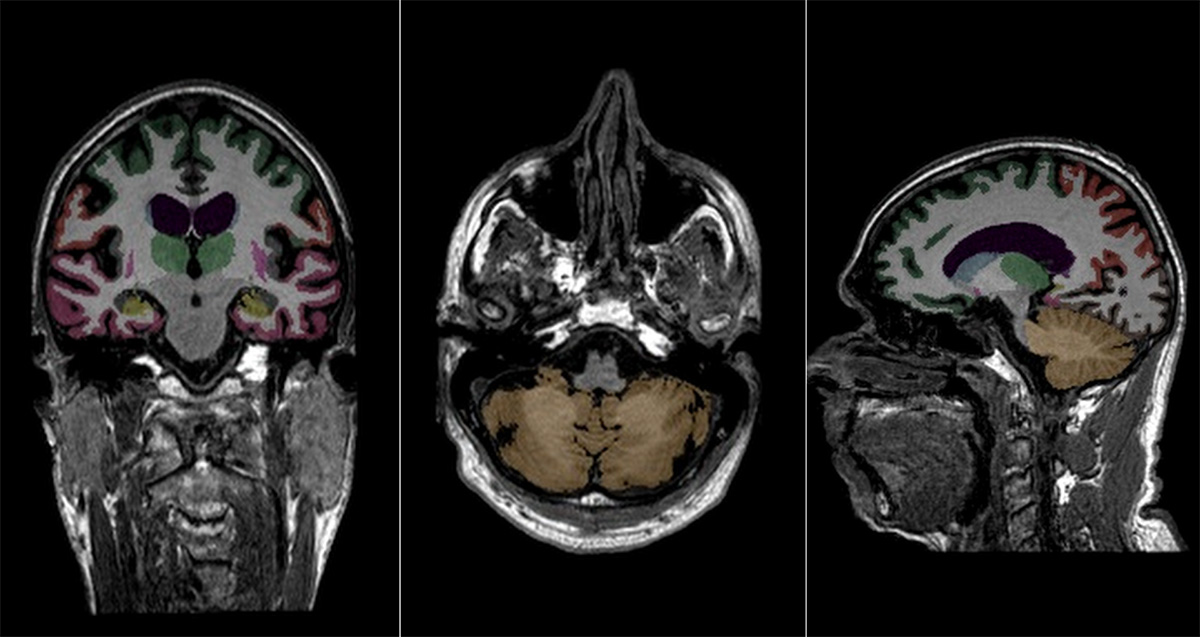

AI-powered brain atrophy quantification

Provides consistent analysis with automated, objective quantification of brain structures, volumetric analysis, and atrophy measurements.

Color-coded anatomical overlays on T1 images and standard PACS viewers enable immediate visual assessment of brain structure.

Provides automated segmentation of brain structures and accurate assessment of changes in volume.

Delivers quantitative measurements of region volume for comparison to prior exams and normative age- and sex- matched databases with percentile rankings that identify deviations from expectations.